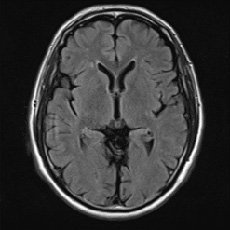

• 頭部MRI正常

正常